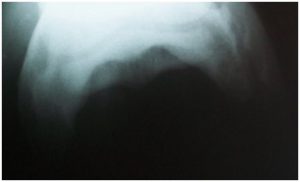

- Diagnostic imaging- radiography or ultrasound

- Radiography, ultrasound

Waverly Equine Services has a top of the line portable digital x-ray system allowing for instant high-quality x-ray images. Digital radiography is one of several valuable diagnostic tools that allow an equine veterinarian to see changes inside your horse. X-rays are commonly used in diagnosing causes of lameness such as navicular disease, OCD, and osteoarthritis. They are also used to diagnose conditions such as tooth abscesses, sinus infections, kissing spine, cervical arthritis and much more. Radiography has been fundamental in equine diagnostic imaging for years and digital radiography takes it to another level.